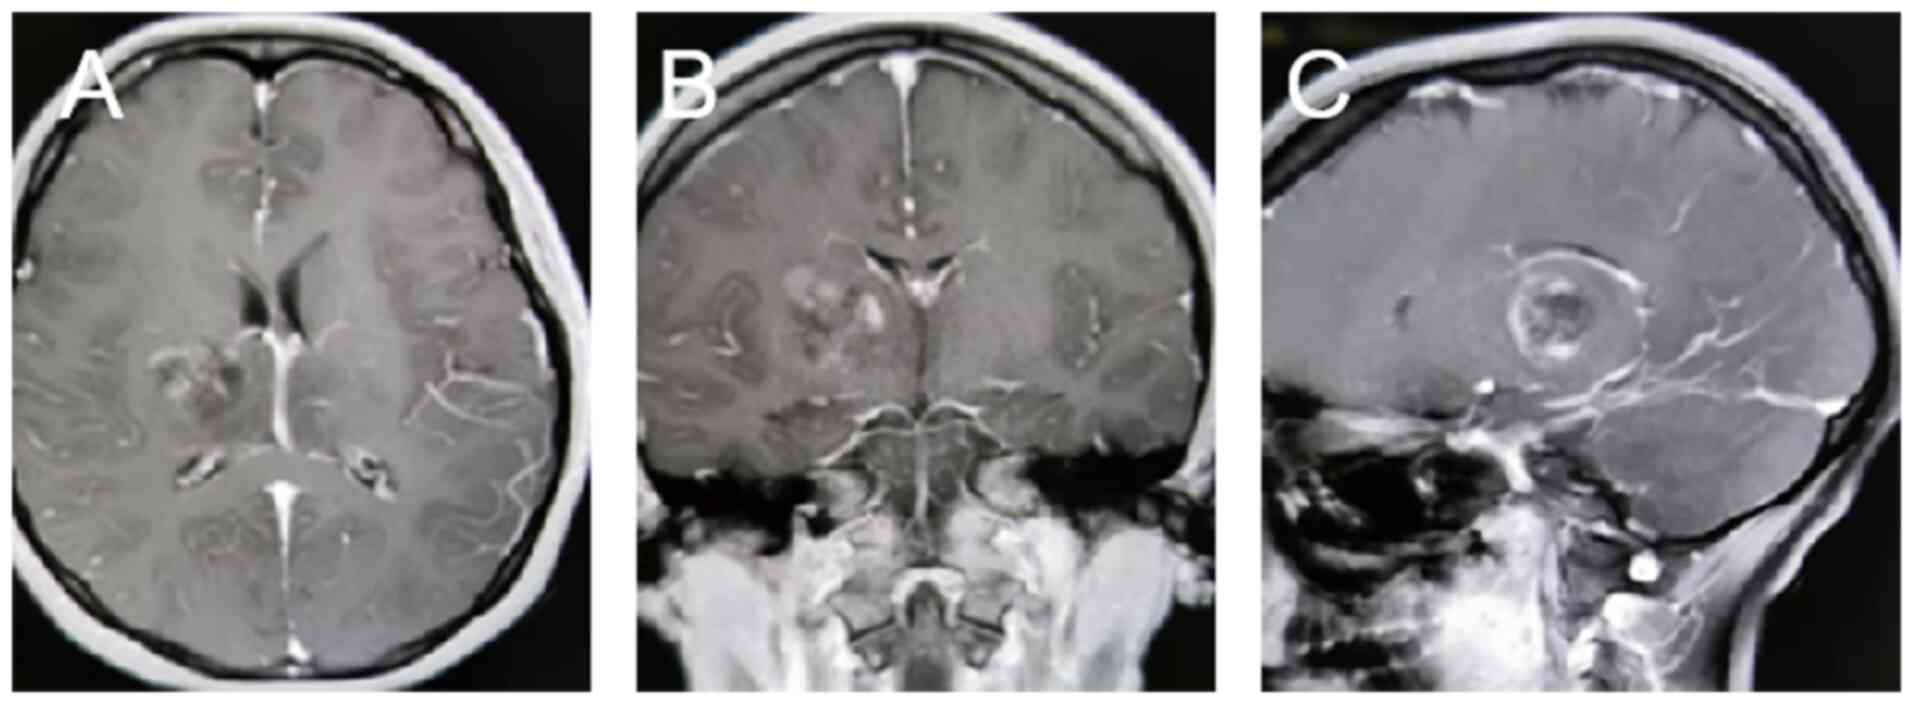

Personalized combination therapy for diffuse midline glioma: A case report

The present study aimed to analyze the efficacy of personalized combination therapy for patients with H3K27M mutant diffuse midline glioma (DMG) so as to explore new treatment options for further clinical research. The clinical data and prognosis of a patient with H3K27M mutant DMG are summarized and discussed in the context of the relevant literature. The patient was a 20‑year‑old female diagnosed with DMG treated with a combination of surgery, radiotherapy, chemotherapy, electric field therapy, immunotherapy and targeted therapy. An overall survival time of 28 months was achieved. In summary, personalized treatment strategies are expected to provide longer‑lasting survival benefits for patients with DMG.